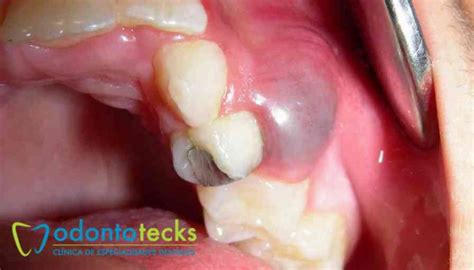

Los quistes en los dientes reciben el nombre profesional de quistes odontogénicos. Un quiste bucal es una especie de saco o cavidad patológica que se forma en los tejidos de la boca. Está revestido por una membrana interna y contiene líquido, aire o material semisólido en su interior.

En su interior, están formados por pus, que es un material que puede estar en estado semisólido o también en estado líquido. Se trata de unas cavidades que como hemos mencionado suelen ser una extensión de una infección que se ha producido en los dientes o huesos adyacentes.

- Inflamación o hinchazón: Cuando un quiste crece dentro del hueso maxilar (como un quiste dentígero o radicular grande), puede provocar una inflamación visible en la encía o incluso una leve hinchazón facial en la zona.

- Quistes dentales radiculares: Es el quiste dental que más frecuentemente nos encontramos en nuestra clínica dental. Hacen referencia a aquellos quistes que se encuentran en la punta de la raíz de los dientes. Aparecen cuando existen grandes caries en los dientes que afectan a la pulpa dental o también llamado nervio dental. Y también son frecuentes en dientes endodonciados.